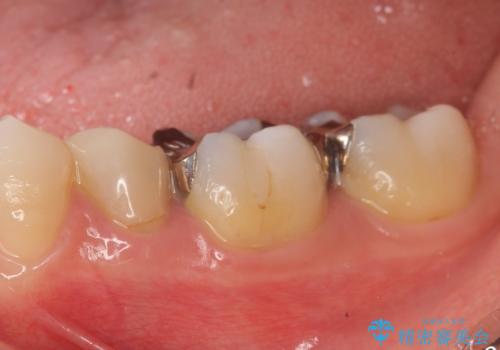

- 左下奥歯の銀歯が気になると来院された方の症例です。

左下7はセラミックインレーによる修復を行い、左下5、6はオールセラミッククラウンによる補綴を行いました。